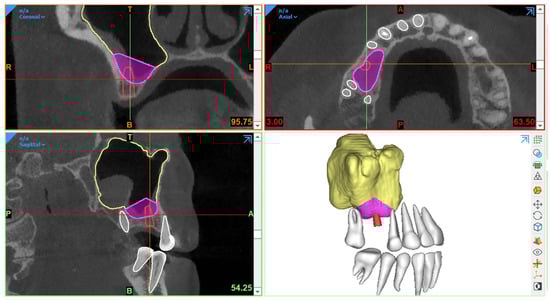

Generally, CBCT images are saved in a Digital Imaging and Communications in Medicine (DICOM) format, which is then transferred to 3D software programs for further processing to plan the procedure. The most essential step in SFE planning workflows is segmentation, a process by which the region of interest is extracted from 3D images for generating 3D virtual models. These models are then used for fabricating guides or pre-surgically assessing the amount of required (bone) graft (Figure 1).

Figure 1. Example of graft volume estimation in Mimics (version 23.0, Materialise N.V., Leuven, Belgium) following automated sinus and teeth segmentation (creator.relu.eu, Relu, BV, Version March 2023).